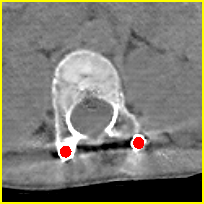

Effect of metal mask projection (SE0-Net vs SE-Net). From Table 1, we can observe the use of instead of improves the performance for at least 4.1 dB in PNSR and reduces MSE from 0.95219 to 0.00074 for all metal sizes. The groups with large metal implants benefit more than groups with small metal implants. As shown in Fig. 4, the artifacts in metal trace of SE0-Net are over-removed or under-removed, which introduces bright and dark bands in the reconstructed CT image. With the help of , SE-Net can suppress the artifacts even when the metallic implants are large and the surrogate data are more consistent with the correct data outside the metal trace.

Effect of sinogram padding (SE-Net vs SEp-Net). Sinogram padding mainly improves the performance in the group with the largest metal objects, with a PSNR gain of 0.15 dB and an MSE reduction of 0.00048. As shown in Fig. 4, the model with sinogram padding restores finer details of soft tissue between large metallic objects because more correct information is retained by periodic padding than zero-padding.

Effect of learning with (SEp-IE-Net vs Ours). When is jointly restored with the corrupted , the sinogram correction performance is affected with an increment of 0.00033 in MSE and of 0.7 dB in PSNR. More details of soft tissue around metal are retained and the image becomes sharper, as shown in Fig. 4.